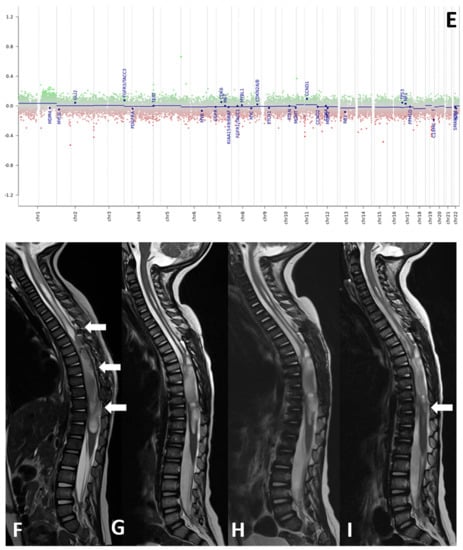

| 7 | 13 | SC | HGG | MEF2D-NTRK1 | NM | GBM pediatric RTK1 type subtype A (score 0.31337) | NA | 8 | A |

| 8 | 30 | LH | HGG | KCTD8-NTRK2 | Plexus tumor, subclass pediatric B (score 0.4) | GBM pediatric RTK1 type, subtype B (score 0.43) | 22 | 162 | A |